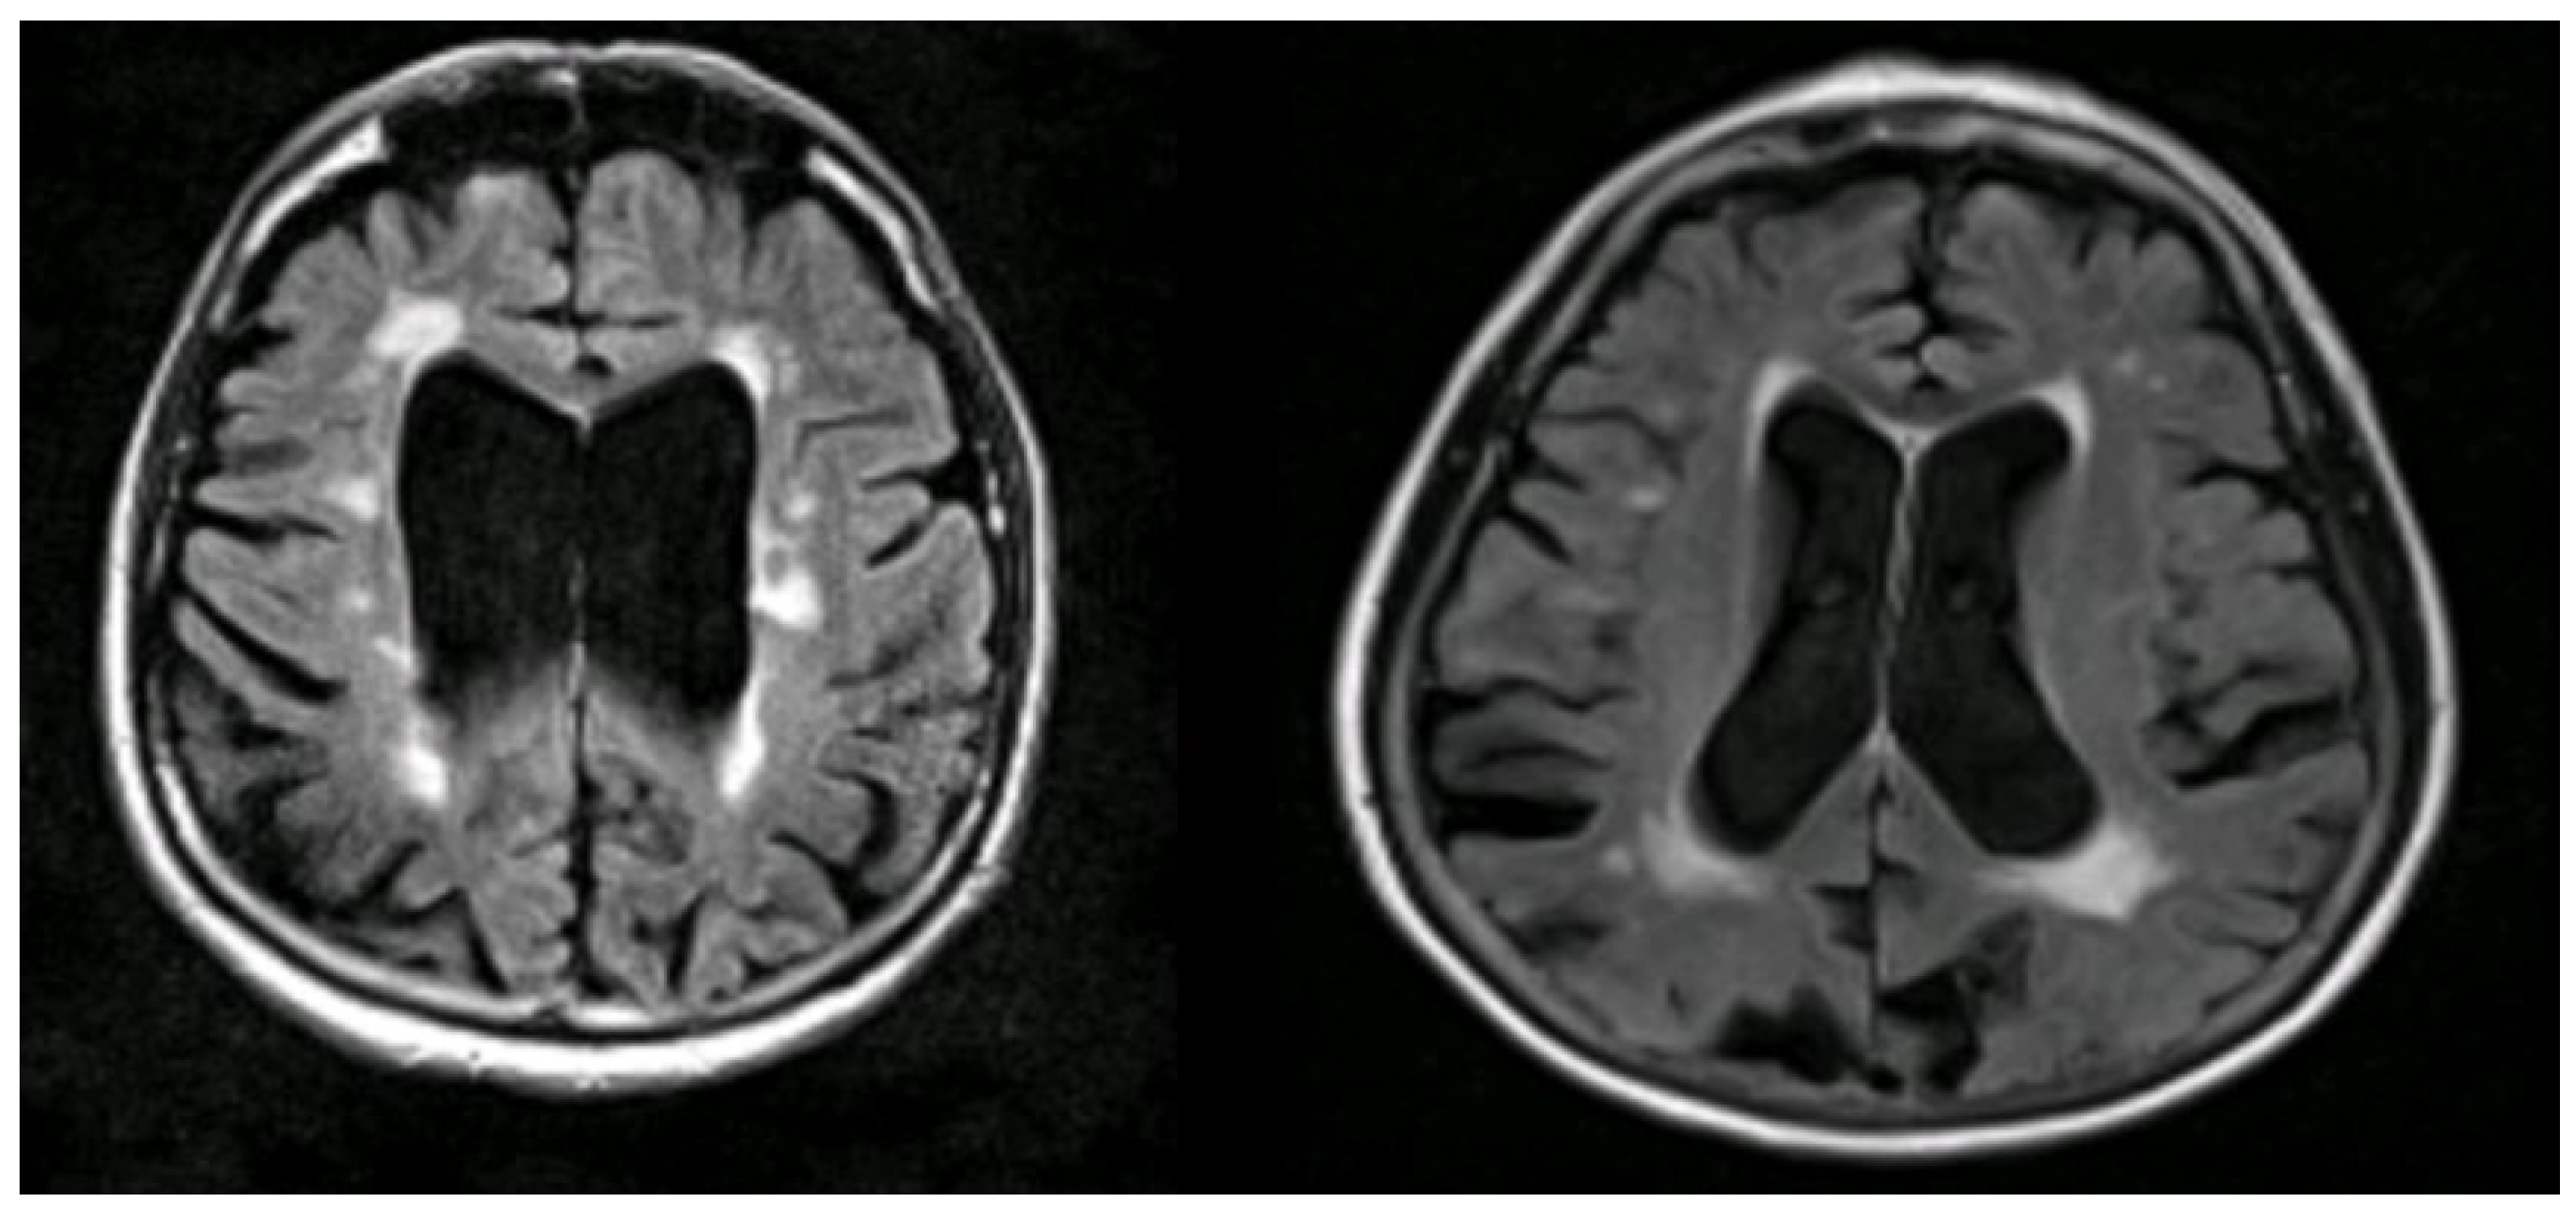

Figure 7.

Illustrations to show co-existing WMHs on MRI in people with AD. The WMH are seen as white areas around the ventricles (Courtesy—Jennifer Waymont, University of Aberdeen).